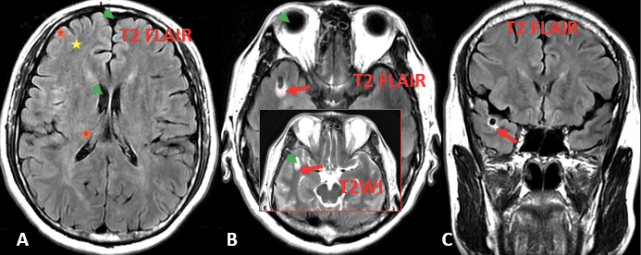

图 5. A. T2 FLAIR 灰白质对比差(红色星和黄色星);脑脊液、玻璃体及病变内囊性成份(自由水)呈明显低信号(绿色箭头);B. 为同层面的 T2 FLAIR 和 T2WI 显示病变周围水肿(结合水)仍呈稍高信号(红色箭);C. 冠状位为 T2 FLAIR